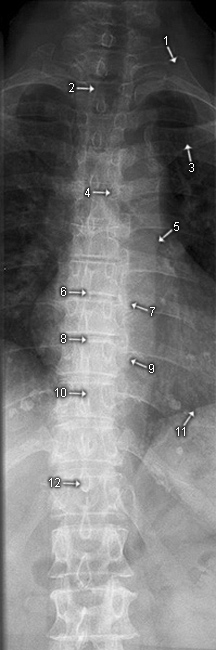

BWS a.p.

1. Costa I (1. Rippe)

2. Trachea

3. Clavicula

4. Pediculus arcus vertebrae

5. Paravertebrallinie

6. Wirbelkörpergrundplatte

7. Caput costae

8. Wirbelkörperdeckplatte

9. Processus transversus

10. Corpus vertebrae (Wirbelkörper)

11. Diaphragma (Zwerchfell)

12. Processus spinosus

BWS seitlich

1. hintere obere Abschlusskante

2. vordere obere Abschlusskante

3. hintere untere Abschlusskante

4. vordere untere Abschlusskante

5. Processus transversus

6. Wirbelkörperdeckplatte

7. Zwichenwirbelraum

8. Wirbelkörpergrundplatte

9. Foramen intervertebrale

10. Processus spinosus

11. Corpus vertebrae

12. Diaphragma (Zwerchfell)

13. Articulatio intervertebralis